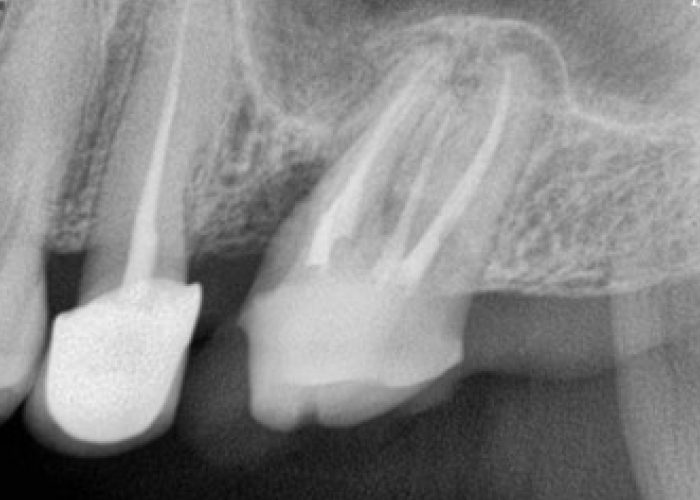

충치치료 전후 사례

• 치료전

치료후